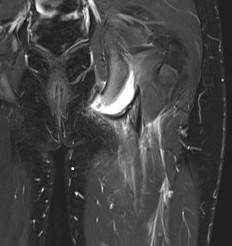

MRI

Ischial tuberosity avulsion 3Ischial tuberosity avulsion 2

Indications for surgery

> 1.5 cm displacement